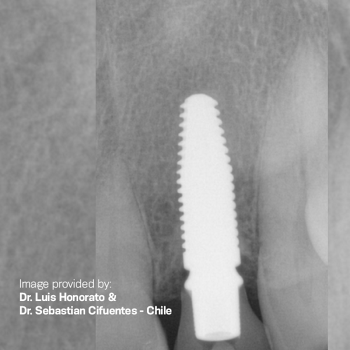

Sistema de Implantes de Cerámica Zi - Una nueva mentalidad

Un diseño moderno y cónico, junto con diversas opciones protésicas, ofrecen resultados impresionantes y tratamientos en el mismo día.

Solución de Implante de Dos Piezas

Tecnología de Vanguardia

Portafolio Protésico

Tratamiento de Superficie SLA

Descubre soluciones que aportarán predictibilidad a tus casos.